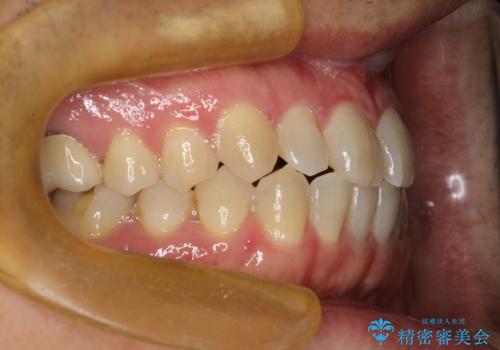

前歯の真ん中の隙間を閉じたい インビザラインによる目立たない矯正

- 上顎の正中の隙間が気になるとのことで来院されました。

下の歯と歯の間をわずかに削り、スペースを作り、正中の隙間を閉じる計画としました。

装置はインビザラインにて行いました。

インビザラインで目立たずに矯正治療を行うことができました。

使用時間を守っていただけたので、比較的スムーズに矯正を終了することができました。